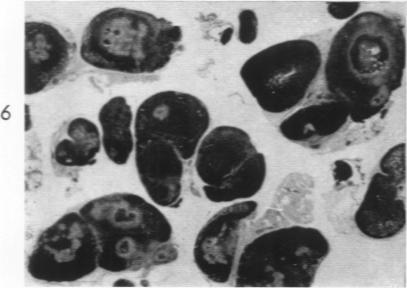

Studies on the mechanism of altered susceptibility to experimental allergic encephalomyelitis.

Am J Pathol. 1961 Oct;39(4):419-41.